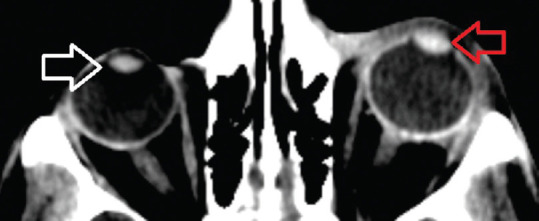

Results: Out of 190 injured globes, the final clinical diagnosis confirmed 54 (28.4%) open globe injuries and 136 (71.5%) closed globe injuries. Between the two groups, intraocular hemorrhage, lens dislocation, lens injury or absence, intraocular foreign body, intraocular air, wall/contour defect, and ACD change were considered statistically significant (P < 0.05). The average sensitivity, specificity, positive predictive value, negative predictive value, and accuracy of CT in diagnosing open globe injury were 71.3%, 98.5%, 83.6%, 95.75%, and 94.9%, respectively.

Conclusion: Globe contour deformity or defect, intraocular hemorrhage, and a change in ACD were the three most predictive signs of open globe injury. CT is of valuable help in a multi-trauma setting and in an uncooperative patient for ophthalmological examination to draw attention to globe injury. However, CT examination alone is insufficient in detecting all cases of open globe injury. There is a need for a more collaborative approach among emergency physicians, ophthalmologists, and radiologists.